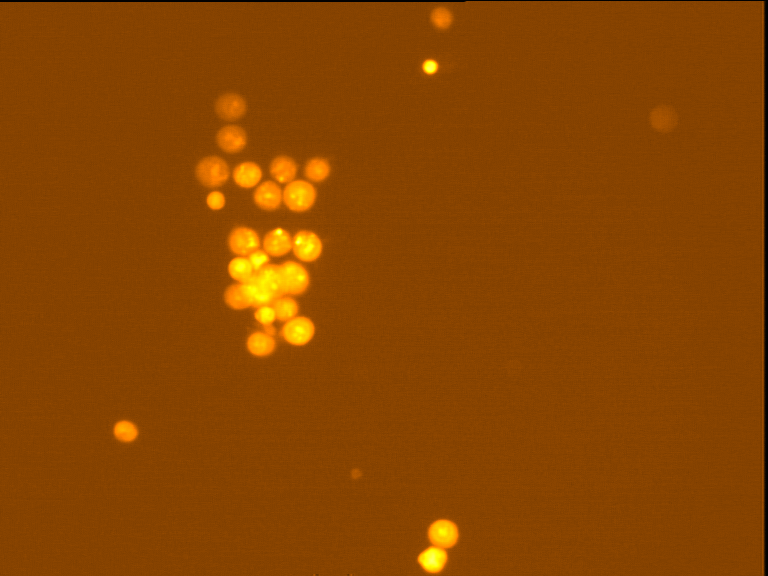

Fig. 4 through 6 show the morphological features of Raji cell sub-lines exposed to DOX, indomethacin, or verapamil. Some of the reversal agents significantly increased the frequency of apoptotic cells compared with control cells. Thus, the P-gp reversal agents were able to overcome apoptotic resistance in the NHL cell-line model. Apoptotic cells in the controls contributed approximately 10% of the whole population (i. e., 61/600 x 100 = 10.16% for TK+ and 69/600 x 100 = 11.5% for TK-). After exposure to the P-gp reversal agents, apoptic cells increased to 22.3% with indomethacin and to 43% with doxorubicin in TK+ cells. In TK- cells, apoptic cells increased from 11.5% to 26.8% and 75.7% with indomethacin and doxorubicin, respectively.

Fig. 5: Morphological features of Raji TK+ cells after treatment with indomethacin (1), verapamil (2) and DOX (3). In each row, left images show intact cells, middle images show apoptotic cells, and right images show necrotic cells as they appeared under the microscope X 200

Fig. 6: Morphological features of Raji TK- cells after treatment with indomethacin (1), verapamil (2), and DOX (3). In each row, left images show intact cells, middle images show apoptotic cells, and right images show necrotic cells as they appeared under the microscope X 200